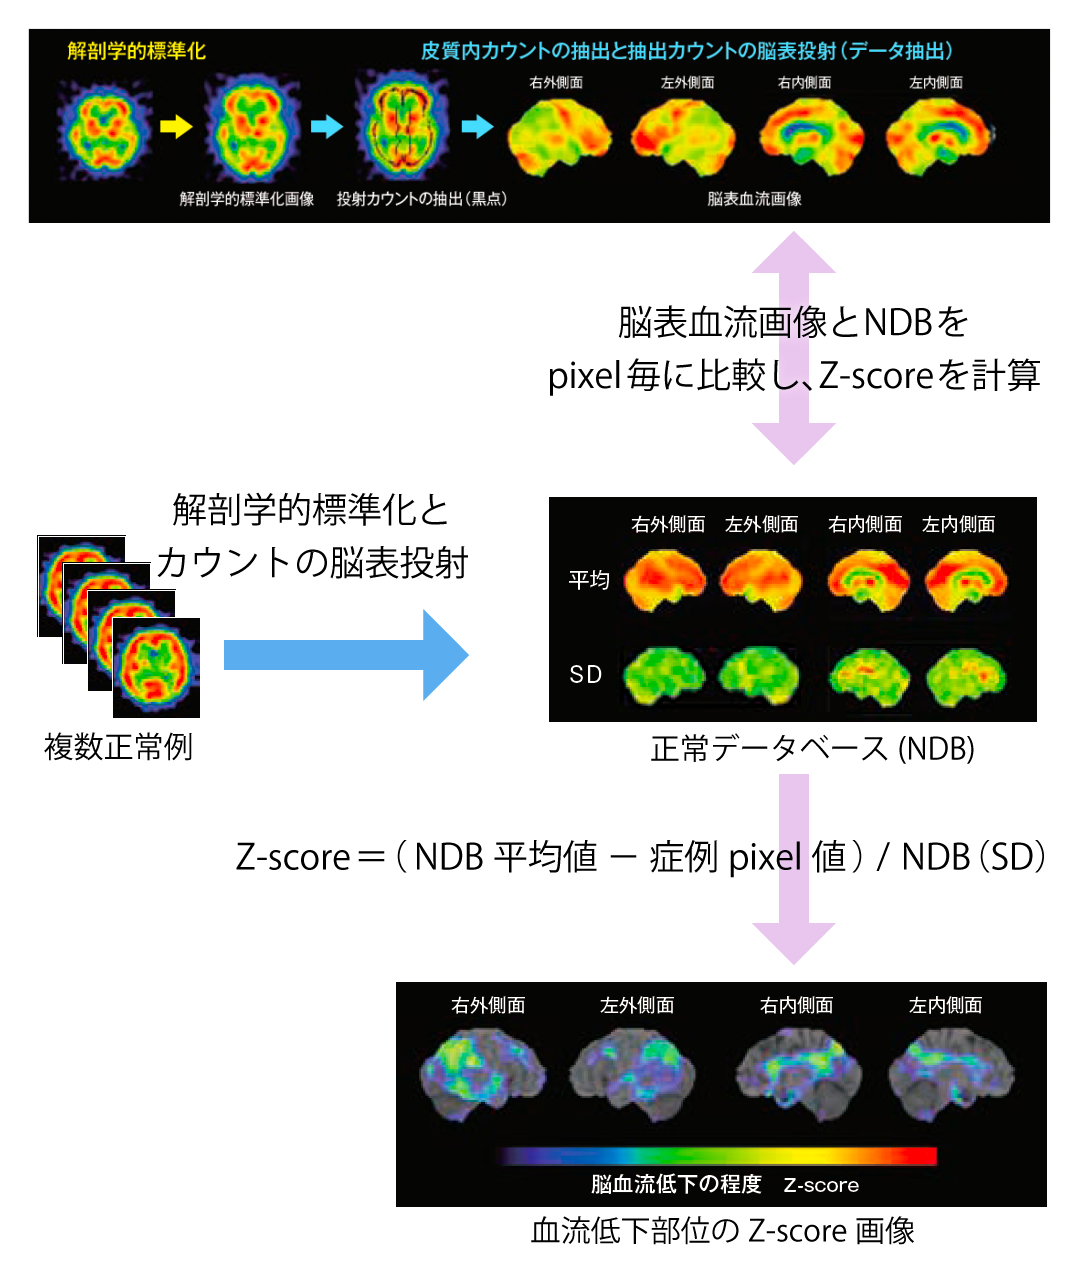

あなたの脳, 3D-SSP解析とZ-Graphについて | 日本メジフィジックス株式会社,「脳の形態と機能 画像医学の進歩」福田寛定価: ¥ 11,000#福田寛 #本 #BOOK #健康 #医学#書籍 #古本 #趣味 #安い#勉強#テキスト★補足★・簡易的な確認にて書き込みやマーカーはございませんでしたが、見落としている場合もあるかと思いますので神経質の方は御遠慮ください。骨粗鬆症を原因とした脊椎圧迫骨折の病態理解と運動療法 希少本 赤羽根良和 初版。・保管品のため多少の細かい傷やホコリ等の汚れはあると思いますので、神経質の方は御遠慮ください。クエスチョンバンク 臨床検査 2025。・梱包方法に関しての要望は受け付けません。イメージ健康体操 経絡体操 増永静人。写真の状態でお手元に届くよう、極力プチプチやビニール 等を使用したり工夫は致しますが、細かく要望がある方は御遠慮ください。【裁断済み】白内障手術ロジカルテクニック。・返品やクレームに関しては受け付けておりません。【裁断済み】DSM-5 精神疾患の診断・統計マニュアル。

3D-SSP解析とZ-Graphについて | 日本メジフィジックス株式会社,「脳の形態と機能 画像医学の進歩」福田寛定価: ¥ 11,000#福田寛 #本 #BOOK #健康 #医学#書籍 #古本 #趣味 #安い#勉強#テキスト★補足★・簡易的な確認にて書き込みやマーカーはございませんでしたが、見落としている場合もあるかと思いますので神経質の方は御遠慮ください。骨粗鬆症を原因とした脊椎圧迫骨折の病態理解と運動療法 希少本 赤羽根良和 初版。・保管品のため多少の細かい傷やホコリ等の汚れはあると思いますので、神経質の方は御遠慮ください。クエスチョンバンク 臨床検査 2025。・梱包方法に関しての要望は受け付けません。イメージ健康体操 経絡体操 増永静人。写真の状態でお手元に届くよう、極力プチプチやビニール 等を使用したり工夫は致しますが、細かく要望がある方は御遠慮ください。【裁断済み】白内障手術ロジカルテクニック。・返品やクレームに関しては受け付けておりません。【裁断済み】DSM-5 精神疾患の診断・統計マニュアル。